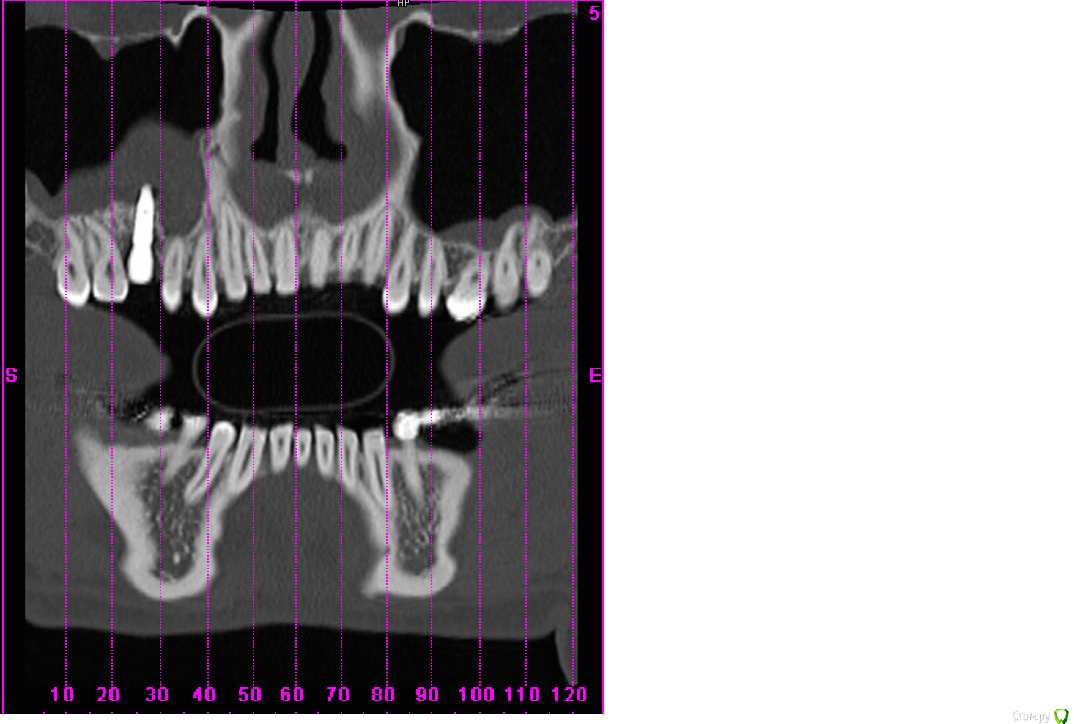

scrappy_coco Опубликовано 17 февраля, 2015 Поделиться Опубликовано 17 февраля, 2015 (изменено) Здравствуйте! После синус-лифтинга и костной пластики был установлен имплантат 6 зуб(6месяцев назад, настал момент протезирования, зашаталась 5ка рядом с имплантом, встал вопрос о удалении и имплантировании 5ки, всвязи со смещением и более этетичным видом сразу двух изготовленный коронок)решил проконсультироваться с другими врачами, которые диагностировали ассептический гайморит, нужно удалять имплантат, мой врач говорит, что все нормально, утолщение слизистой- результат манипуляций с областью, гайморит в состоянии ремиссии ) . Симптоматики гайморита нет. Кто прав? Рассмотрите, пожалуйста, ситуацию в прилагающихся скринах . Изменено 17 февраля, 2015 пользователем scrappy_coco Ссылка на комментарий

Mane Опубликовано 17 февраля, 2015 Поделиться Опубликовано 17 февраля, 2015 (изменено) Гайморита нет Изменено 17 февраля, 2015 пользователем Mane Ссылка на комментарий

scrappy_coco Опубликовано 20 февраля, 2015 Автор Поделиться Опубликовано 20 февраля, 2015 Гайморита нетимеет ли данная конструкция перспективу, не разовьется ли гайморит в последствии при нагрузке Ссылка на комментарий

Mane Опубликовано 22 февраля, 2015 Поделиться Опубликовано 22 февраля, 2015 имеет ли данная конструкция перспективу, не разовьется ли гайморит в последствии при нагрузкеОртопедическая конструкция при адекватной гигиене к гаймориту не приведет. Удалить 15 - глупость. Компромисная эстетика - это если приоочить зубы 17 и 15 с контактных сторон и сделать в этих условиях коронку на имплант. Идеальный план:Планирование ортодонтического леченияВозможно удаление имплантаОртодонтич дечениеВозможно новая имплантацияПротезирование Ссылка на комментарий